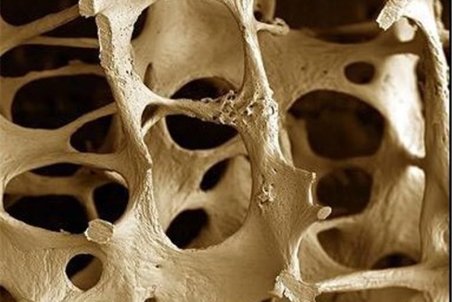

یکی از علل مهم مرگ و میر در سراسر دنیا پوکی استخوان است. استخوان بافت زندهای است که مدام در حال تخریب و بازسازی است اما معمولا از سن 35 تا 40 سالگی به بعد جذب کلسیم کم شده و به علت برداشت کلسیم از استخوان، پوکی استخوان شروع میشود و به دنبال آن افزایش احتمال

قدرت استخوانهای بدن ما را ۲ عامل اصلی تراکم استخوان و کیفیت استخوان تعیین میکند. پوکی استخوان یک بیماری عمومی استخوان است که با توده استخوانی پایین و تخریب زیرساخت بافت استخوانی و متعاقبا افزایش شکنندگی و مستعد شدن به شکستگی همراه است. تشخیص پوکی استخوان با

دردی خاموش به نام "آستئوپروز"

بیماری پوکی استخوان یا «آستئوپروز» معروف به درد خاموش، عارضهای است که در آن، تراکم سلولهای استخوانی کم و از قدرت طبیعی آن کاسته میشود و در این حالت استخوان شکننده خواهد شد و احتمال شکستگی حتی بر اثر ضربات کوچک افزایش مییابد.